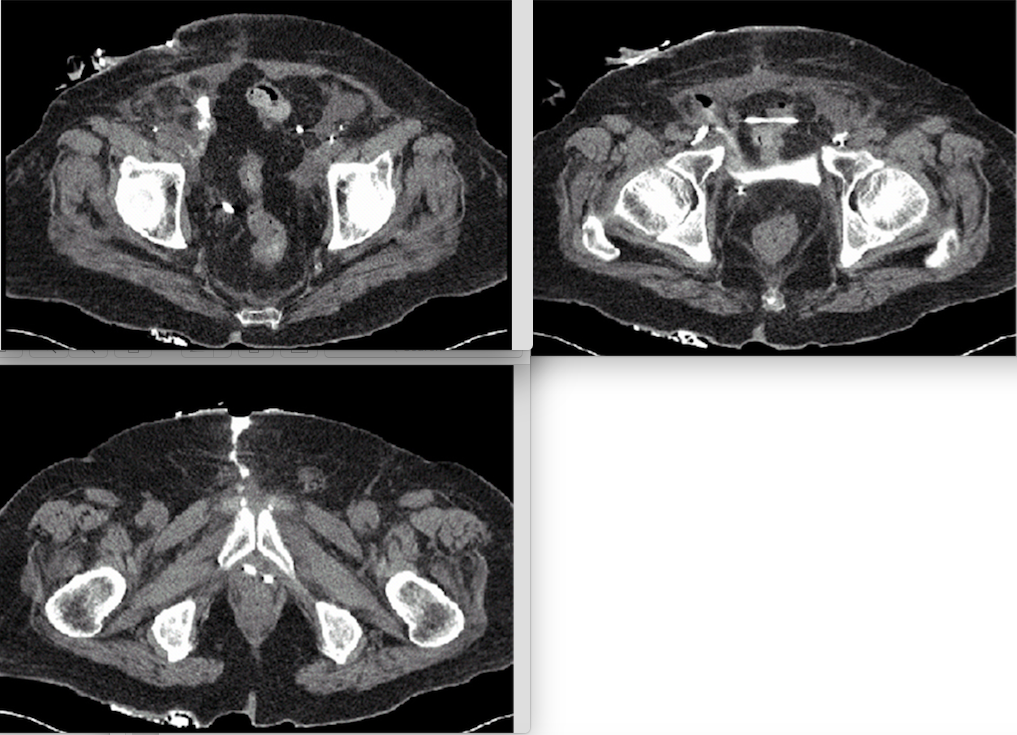

A 77-year-old man has a retracted stoma and clear fluid leaking from his midline incision three weeks after radical cystectomy and ileal conduit diversion. Three images from a CT loopogram are shown. The next step is percutaneous pelvic drainage and:

1

A delayed urinary leak following urinary reconstruction should lead the clinician to suspect tissue ischemia/necrosis. In these cases, the leak is unlikely to resolve with observation alone. Fascial repair is unnecessary unless signs of dehiscence are present. Maximal drainage of the reconstructed segment is essential in order to minimize the output of the leak. In this case, the CT image demonstrates leakage from the proximal end of the conduit. Given the presence of stomal retraction, catheter drainage of the conduit may decompress the leak. Given the pooling of contrast in the pelvis, a percutaneous drain is also advisable in order to control the fistula, minimize the risk of local abscess, and to protect the fascia from further dehiscence. While this patient may ultimately require stomal revision, it would not be advisable until determining if the leak will heal with conservative therapy. Early exploration and repair is difficult given the intense local inflammatory reaction, and it is likely to result in a high risk of treatment failure given the condition of the local tissues.